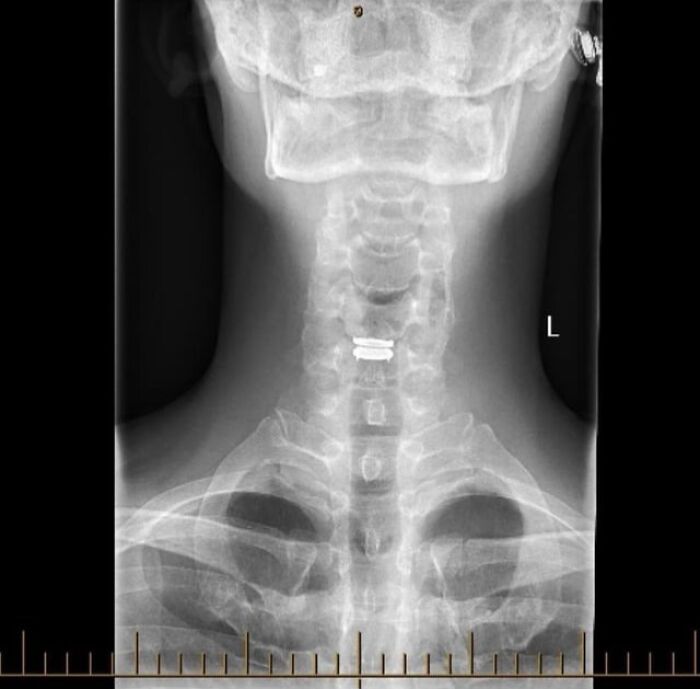

#12 Thought You Good People Might Like To See My New C5/C6 Disc

Image credits: medical